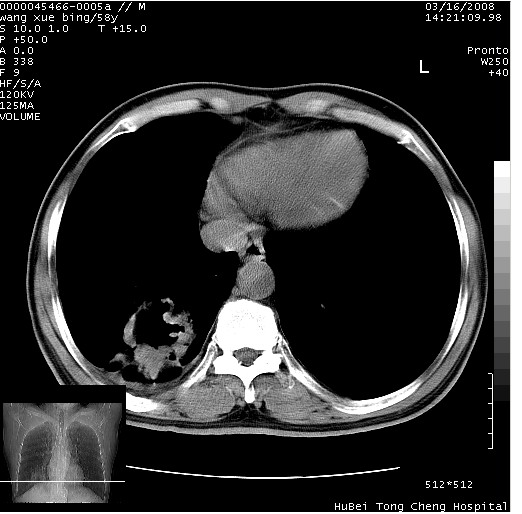

患者 男,58岁。咳嗽、咯血3月余。

胸部cr x线片提示:1)右下肺脓肿。2)右下肺周围型肺癌不排除。建议:行ct扫描检查。

胸部ct轴位平扫(层厚10mm,螺距1.5,重建间隔10mm),图像如下:

右肺下叶团块及不规则空洞,内壁不规则,外缘见粗长毛刺,临近胸膜明显增厚并与病灶关系密切。支持考虑:右肺肺脓肿!建议穿刺病理检查待除外周围型肺癌!

右肺下叶见不规则厚壁空洞,内壁不规则,外缘见粗长毛刺,临近胸膜明显增厚并与病灶关系密切。支持考虑:周围型肺癌!

考虑右下肺中心型肺癌并远端阻塞性炎症及胸膜及纵隔淋巴转移

右肺下叶周围型肺癌伴空洞形成!征象比较明显!分叶、毛刺、胸膜凹陷征、厚壁空洞,壁结节!

空洞壁厚,不规则,其内可见壁结节,周围可见毛刺及阻塞性炎变,多考虑癌性病变.

支持癌性空洞并远端阻塞性炎症